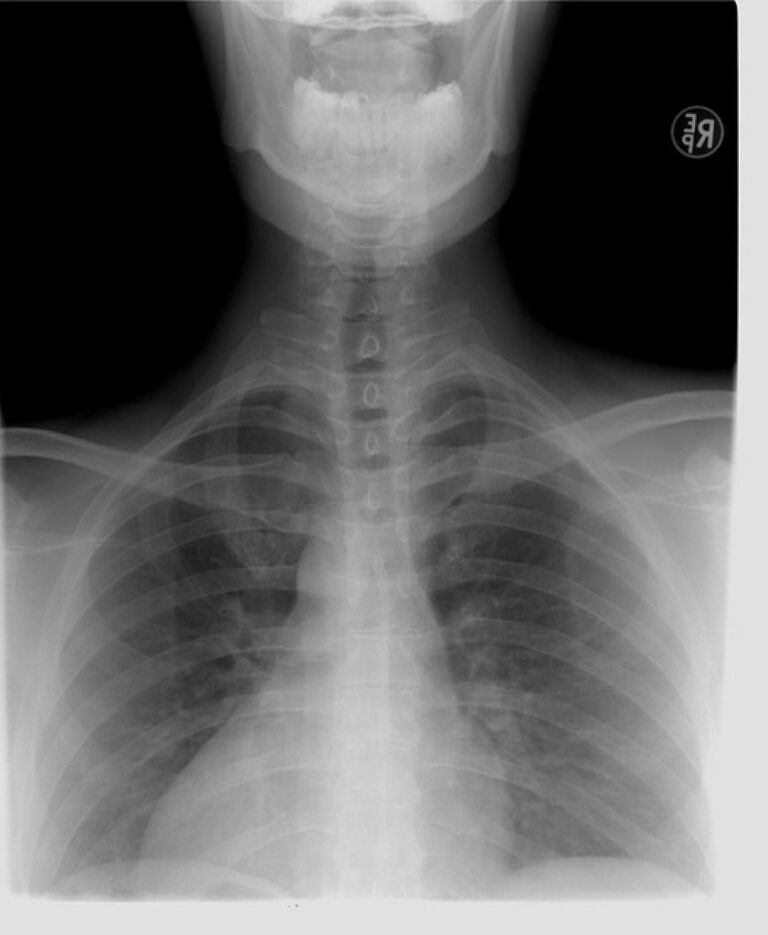

兩處 UCC 均具備 X 光、超音波及基礎檢驗設備,若醫師判斷需進一步治療,也能透過「綠色通道」立即後送至鄰近醫學中心,讓整體醫療流程更順暢。